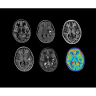

Стандартный пакет приложений SIGNA Works позволит вам достичь желаемых результатов в клинической практике благодаря набору высокоэффективных средств визуализации. Программные приложения, входящие в состав данных клинических пакетов, включают широкий спектр контрастов, функции обработки 2D- и 3D-данных, а также возможность коррекции артефактов движения. SIGNA Works предоставляет набор инструментов, необходимых для проведения эффективного клинического исследования.

• NeuroWorks — универсальное решение для визуализации анатомии головного мозга, позвоночника, сосудов и периферических нервов с четкой дифференциацией тканей.

• ImageWorks — повысит производительность МРТ благодаря визуализации высокого качества с MAGIC, четкими результатами пост-процессинга с READYView.